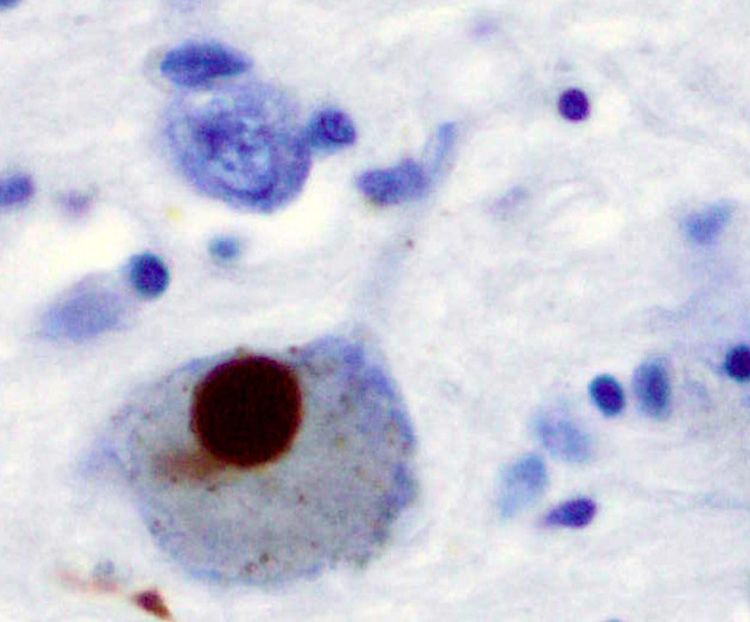

A brown stain indicating the presence of alpha-synuclein in a Lewy body

Alpha-synuclein stained brown in a Lewy body in the substantia nigra. Credit: Wikimedia images / Marvin 101.

Scientists then attempted to raise antibodies against this so-called problem protein. They examined brain tissue and found alpha-synuclein in Lewy bodies – complex, round inclusions in cells that are the characteristic pathological features of Parkinson's.

However, they also discovered that the protein had spread throughout the brain in end-stage Parkinson’s. Clearly, dopamine cells were just one part of the story.